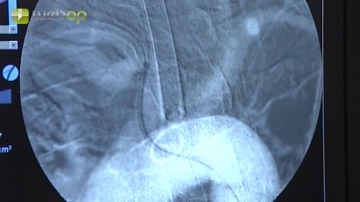

Punktion der A. femoralis rechte Leiste nach Seldinger und vorsichtiges Einführen des Führungsdrahtes. Nach Entfernung der Punktionskanüle Einführen einer 6- oder 7-F-Schleuse unter Durchleuchtungskontrolle. Entfernung des Führungsdrahtes und Kontrolle des pulsatilen Rückstroms, sodann lokale Gabe von 5000 IE Heparin-Kochsalz-Lösung. Unter Duchleuchtungskontrolle Einführen eines langen Terumo®-Drahtes in die rechte Beckenstrombahn und die Aorta.